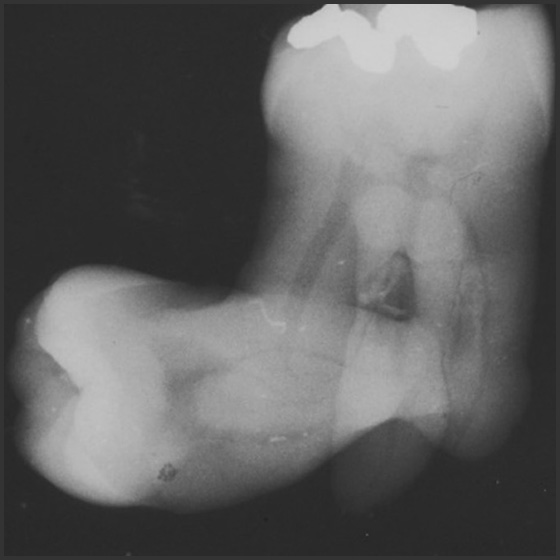

ce513

Radiographic Interpretations [Course Number : 513] Connie M. Kracher, PhD, MSD

The primary objective of this course is to increase your general knowledge of radiographic interpretations by examining case studies.

Anomalies of Tooth Structure (ce651) - Introduction

Anomalies of Tooth Structure [Course Number: 651] Gail F. Williamson, Professor Emerita

The ability to recognize the normal radiographic appearance of the teeth and their component structures is foundational to basic interpretation of intraoral and panoramic radiographic images. It is of equal importance to recognize when the radiographic appearance of the teeth deviates from normal. Dental anomalies associated with tooth structure will be presented to enable the clinician to recognize and identify alterations whether congenital, developmental, or acquired in nature.